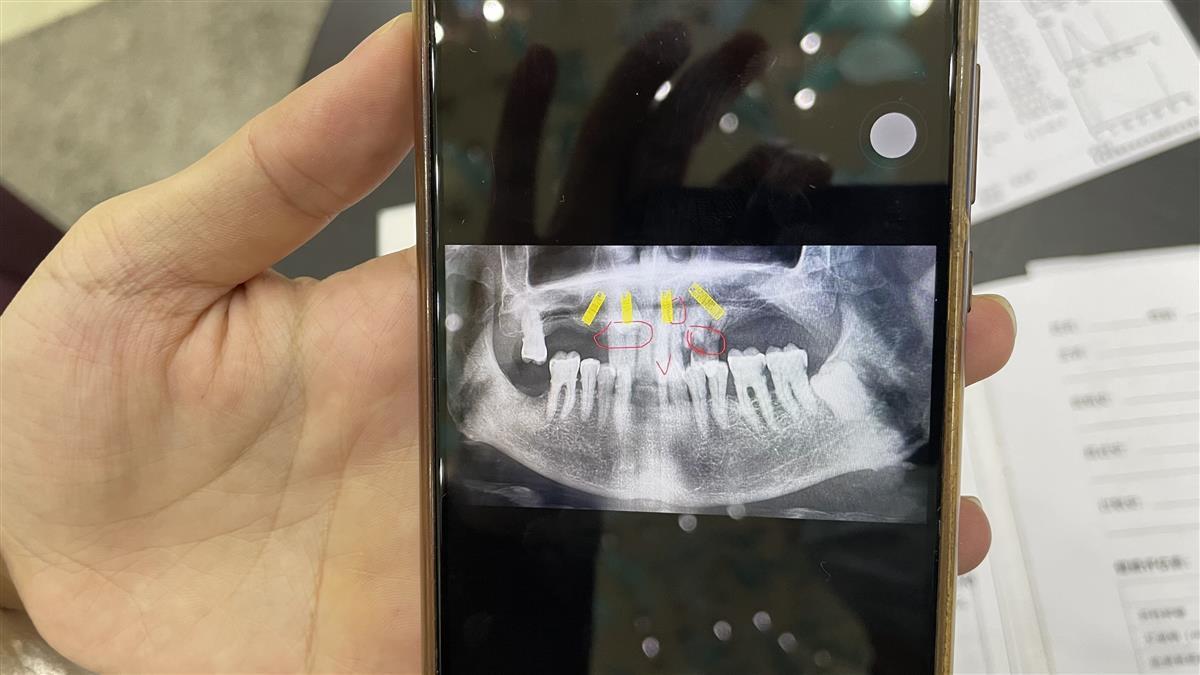

上齒部分前牙區(qū)CT圖

當(dāng)日,極目記者趕到武漢華美整形醫(yī)院,當(dāng)時接待周爹爹的平女士介紹,經(jīng)CT片和現(xiàn)場檢查綜合診斷,周爹爹的上半口牙的前牙區(qū)的8顆牙,有3顆牙已經(jīng)缺損,有2顆松動預(yù)計一年半載后也會出現(xiàn)缺損,余下的3顆,2顆牙為埋伏牙(可理解為殘牙、殘冠),1顆好牙,而周爹爹同意的種植牙方案為對其上齒部分前牙區(qū)種植4顆恢復(fù)上半口14顆牙的半固定修復(fù),這需要對上半口前牙區(qū)的牙齒全部拔除才能處理,所以醫(yī)生才對上半口前牙區(qū)的8顆牙全部進(jìn)行了拔除。

對此,周爹爹稱,院方所說并不屬實,病歷資料中的關(guān)鍵信息也遭到院方動手腳,如醫(yī)院給他提供的8月6日雙方簽定的種植執(zhí)行方案中,建議拔除一欄的信息是空白的,而在醫(yī)院提供給記者的建議撥除中,卻明確寫著建議拔除上半口的殘牙、殘冠。